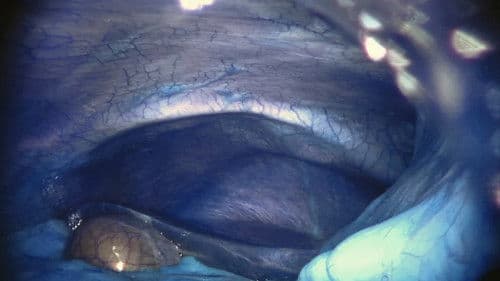

Surgeon

Franca Melfi